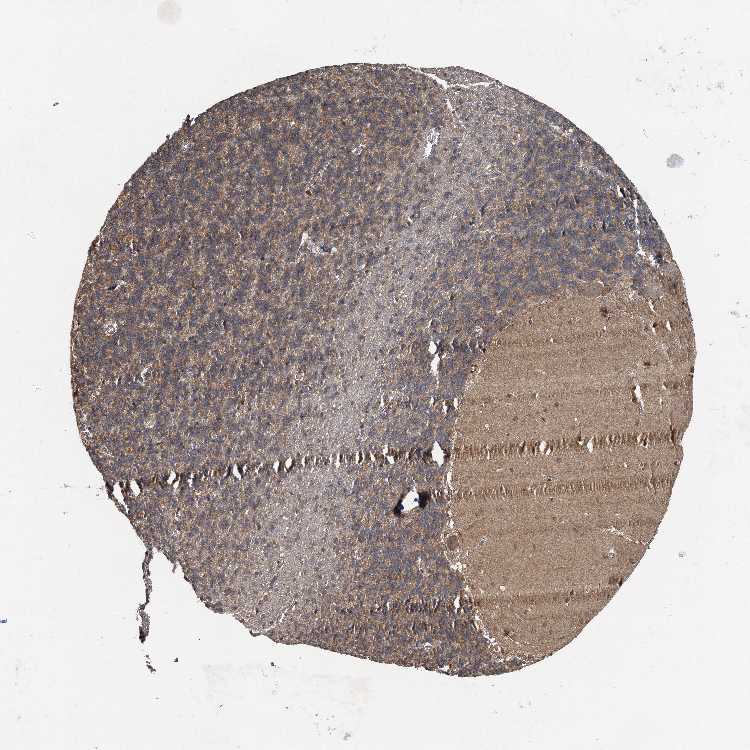

CEREBELLUM - Antibody stainingi

Antibody staining in the annotated cell types in the current human tissue is reported as not detected, low, medium, or high, based on conventional immunohistochemistry profiling in selected tissues. This score is based on the combination of the staining intensity and fraction of stained cells.

Each image is clickable and will lead to virtual microscopy that enables deeper exploration of all samples and also displays staining intensity scores, fraction scores and subcellular localization as well as patient and tissue information for each sample.

Antibody HPA040092

Purkinje cells Medium

Cells in granular layer Medium

Cells in molecular layer Low